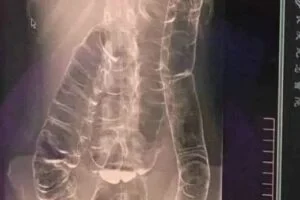

Chronic constipation is a common yet often overlooked condition. In extreme cases, prolonged constipation can lead to toxic megacolon, a life-threatening complication where the colon expands beyond its natural capacity, reaching the chest area and compressing vital organs like the heart.

When the colon is unable to expel waste properly, fecal matter accumulates, causing extreme bloating and distension. Over time, the colon loses its natural folds and ability to contract, resulting in: